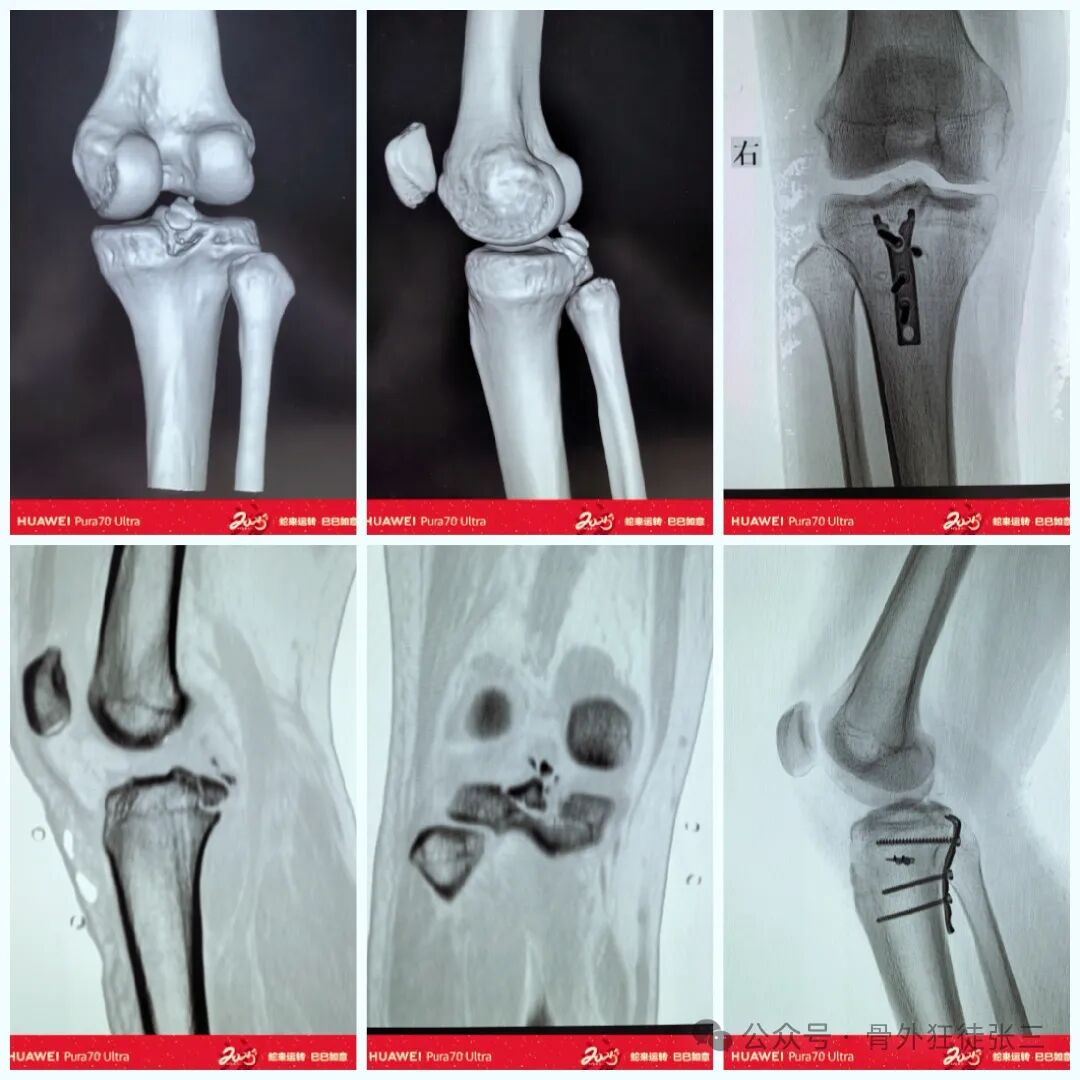

病例二

空心钉+铆钉

病例3

钩板+铆钉

手术切口

取膝关节后方平行腘窝横纹切口,可远端内侧延伸。

切开皮肤和皮下组织及筋膜,找到腓肠肌,沿腓肠肌内侧头中部的肌纤维将其部分切开;用拉钩将腓肠肌内侧头的内部和外部分开,显露后方关节囊并切开,显露撕脱骨折块即可。